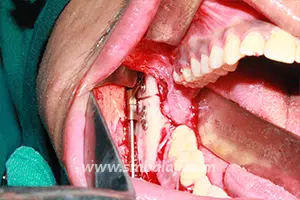

The jaw bone on the deficient side is cut. A sophisticated device called distractor is placed such that the two arms of the device are fixed to the two segments of jaw bone. After a few days, a screw attached to the distractor is turned gradually, ideally at a rate of 1 mm per day. When this is done, the two cut segments move apart and new bone is formed in the resultant gap. After the new bone is stabilized, the distractor device is removed.